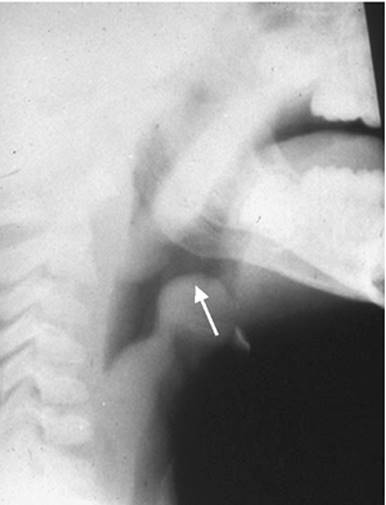

Epiglottitis is an infectious disease of the epiglottis and supraglottis, most commonly bacterial in origin. It usually has a sudden onset, with patients developing high fever, pain with swallowing, drooling due to difficulty handling secretions, and respiratory distress. On presentation the patient is often found sitting in a hunched-forward position with an extended neck and open mouth (sniffing position) (81). On a lateral neck film, edema of the epiglottis and a ballooning of the hypopharynx (thumb sign) will be noted (Fig. 109.8). On direct visualization the epiglottis will appear erythematous (cherry-red) and swollen. Care should be taken with airway manipulation as it may quickly precipitate complete airway obstruction. H. influenzae type b used to be the most common causative agent; however, with the introduction of the vaccine the incidence of H. influenzae–related epiglottitis has significantly decreased (82). Currently S. pneumoniae group A beta-hemolytic streptococci are the most common causative agents (82,83). Epiglottitis is considered an emergency as it has a potential for rapid complete airway obstruction, particularly in children. When epiglottitis is diagnosed, in most cases a secure airway should be established via endotracheal intubation or tracheostomy. The decision to extubate or decannulate is based on clinical improvement. Treatment with intravenous antibiotics (ceftriaxone or ampicillin/sulbactam) and steroids is initiated (81,82). Adults may sometimes present with supraglottitis where the epiglottitis is not involved. In these cases, the airway can often be managed more conservatively, although close in-hospital observation is required.

Figure 109.8. Lateral plain neck radiograph demonstrating edema of the epiglottis associated with epiglottitis.